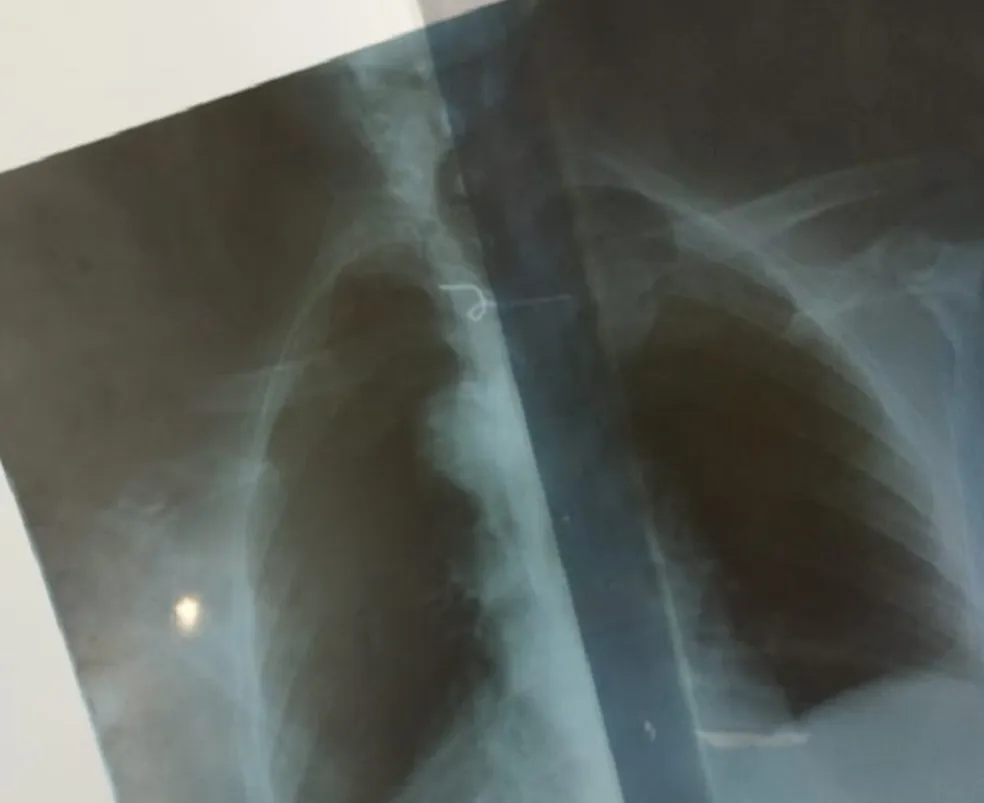

Arame preso a esôfago de idosa no Rio Grande do Norte — Foto: Cedida

Após o engasgo, por volta das 11h da segunda (25), enquanto almoçava, a mulher foi levada para um hospital de São Miguel, onde os profissionais constataram a presença do arame por meio um exame de raio-x.